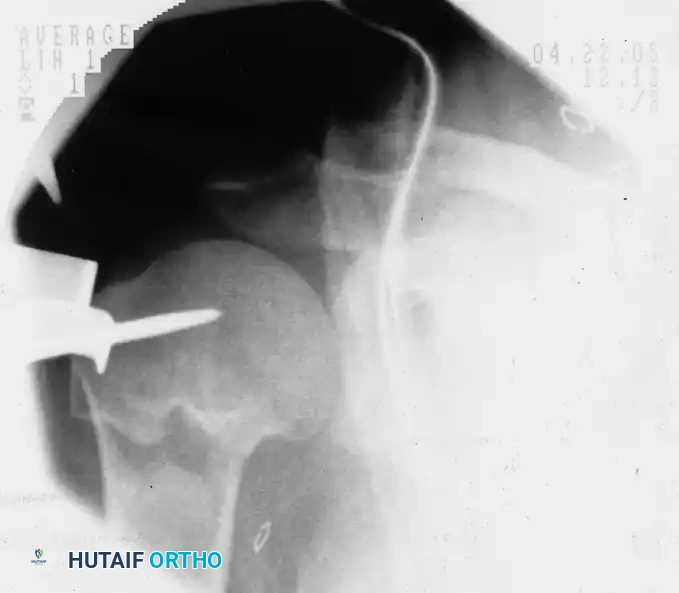

Preoperative fluoroscopic evaluation demonstrating a two-part surgical neck fracture of the proximal humerus, an ideal candidate for the anterolateral approach.

A threaded pin is inserted into the humeral head fragment, serving as a "joystick" to manipulate and reduce the fracture prior to definitive fixation.

Placement of the initial guidewire into the proximal humerus, ensuring the correct entry trajectory for antegrade nailing.

Fluoroscopic confirmation after nail insertion and the placement of multi-planar proximal locking screws.